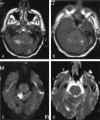

F<sc>ig</sc> 1.

Fig 1.

Patient with isolated restricted diffusion. A and B, DW image (A) and ADC map (B) show restricted diffusion in the PLIC. C and D, Findings on corresponding FLAIR image (C) and contrast-enhanced T1WI (D) are unremarkable.